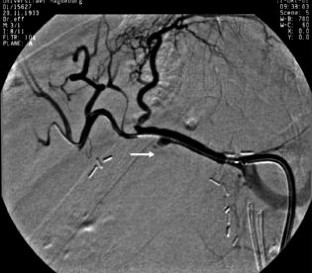

Wir berichten über das diagnostische und therapeutische Vorgehen anhand von 7 Patienten mit Blutungen aus der A. gastroduodenalis (n=5) nach pankreaschirurgischen Interventionen bei Pankreaskopfkarzinom, Rezidiv eines Liposarkoms und chronischer Pankreatitis, der A. hepatica communis (n=1) bei chronischer Pankreatitis und der A. mesenterica superior (n=1) nach akuter Pankreatitis. Anhand von 4 Kasuistiken werden unsere Erfahrungen mit der Implantation von Stentgrafts (Hemobahn®-Prothesen) vermittelt. Den Vorteil der Stentgrafts sehen wir in der sofortigen Blutstillung bei fehlendem Kontakt der Endoprothese zu infiziertem Gewebe und Erhalt der Perfusion des abhängigen Organs. Unsere positiven Erfahrungen mit diesen interventionellen Therapieverfahren erfordern jedoch weitere klinische Untersuchungen, wobei im Mittelpunkt die Indikationen, die technische Erfolgsrate, die stentbedingten Komplikationen und die Langzeitverläufe stehen sollten.

Spontaneous or postoperative hemorrhage into the abdominal cavity due to inflammatory vessel arrosion represents an uncommon but menacing situation. According to the literature, such hemorrhage is associated with a lethality of nearly 2%. Therapeutical options include reoperation and interventional radiological techniques such as endovascular catheter techniques with stent graft implantation or the embolization of vessels. We report on the management of seven cases with hemorrhage either from the gastroduodenal artery (n=5) following pancreatic surgery for pancreatic carcinoma, liposarcoma, and chronic pancreatitis or from the common hepatic artery (n=1) and the superior mesenteric artery (n=1) following chronic pancreatitis. The present article describes our experiences with stent graft implantation (hemobahn prosthesis) in four cases. Based on these experiences, we see the advantages of stent grafts in primary hemostasis without any contact to infected tissue and the preservation of regular perfusion. However, further clinical data are required focussing on indication, technical success rates, stent-related complications, and long-term outcome.